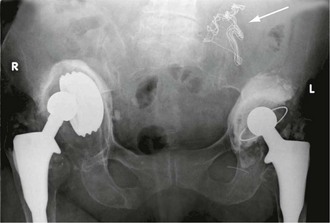

Fig. 5.7 Percutaneous transluminal angioplasty

This man of 55 presented with bilateral calf and thigh claudication. (a) A localised severe stenosis of the distal abdominal aorta. (b) The ‘kissing balloon’ technique used to dilate the stenosis. Two balloons, shown inflated, are used to prevent asymmetrical dilatation which might compromise the opposite common iliac artery